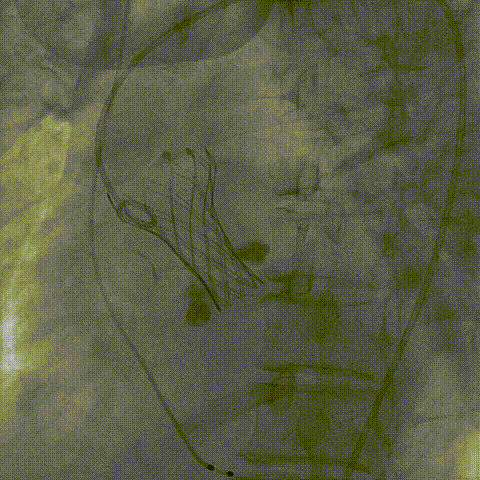

主动脉根部造影

球囊第一次预扩

球囊第二次预扩